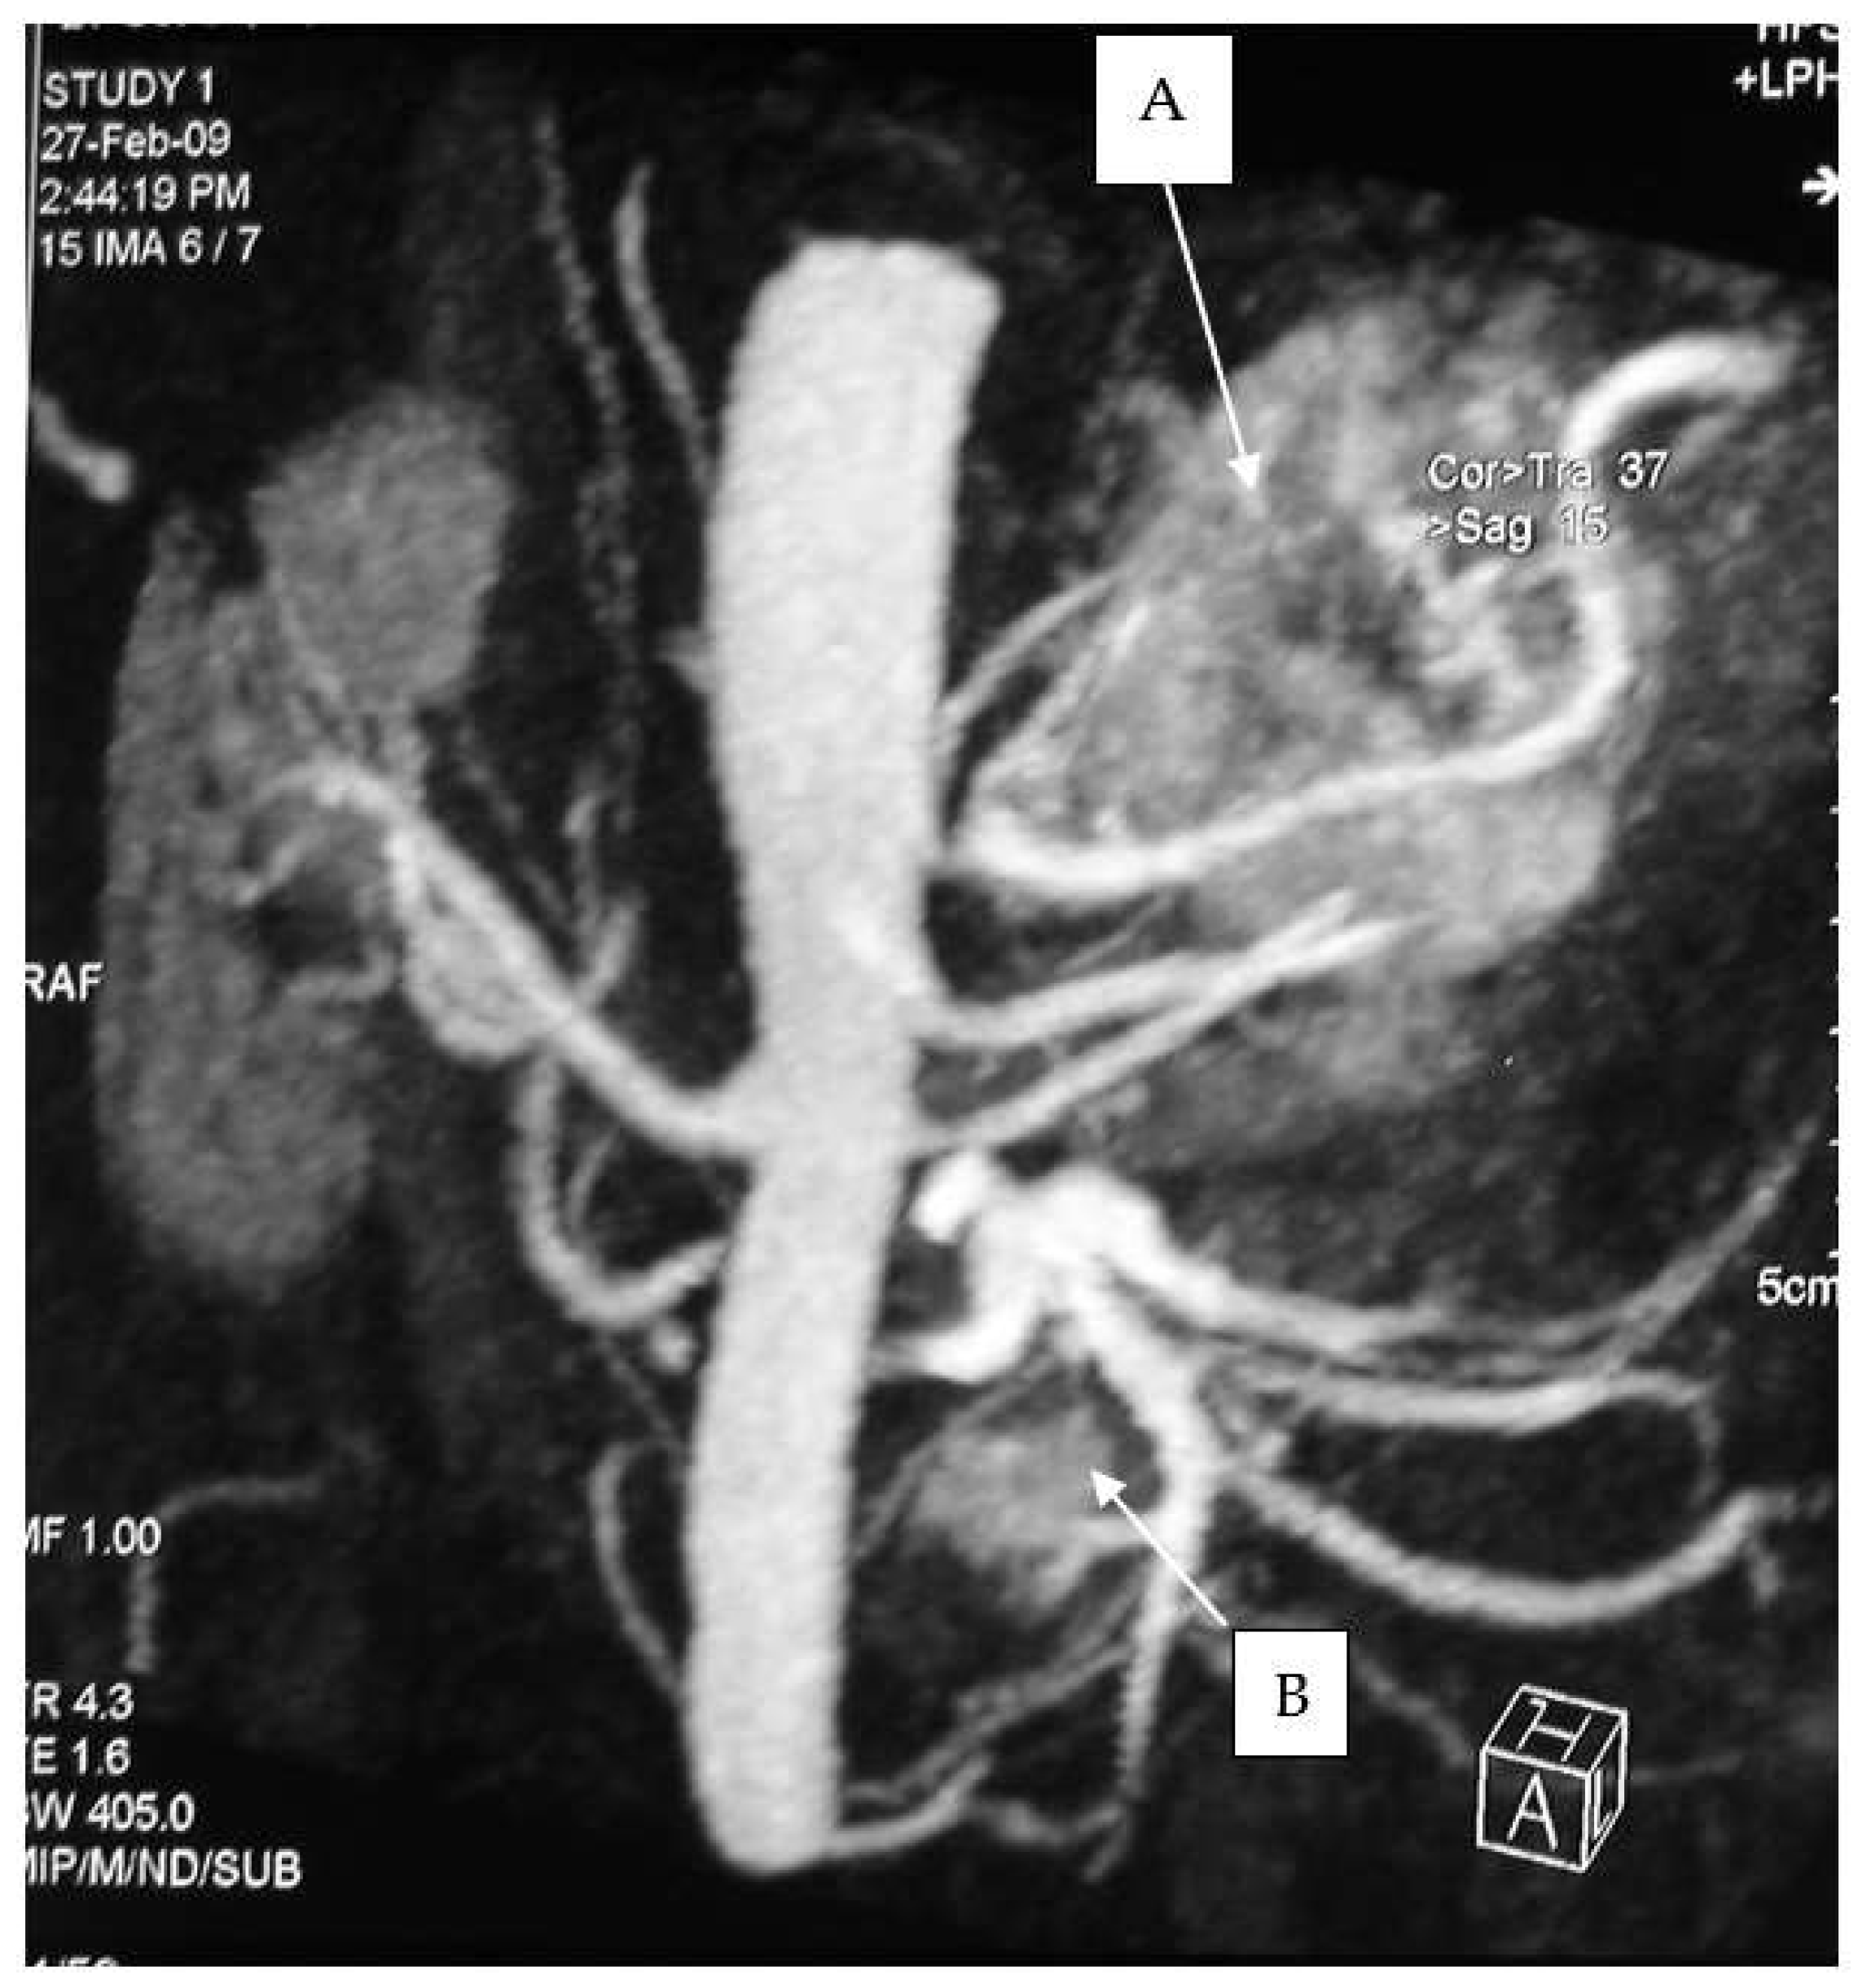

All operations were performed by the same endocrine surgical team. The surgical approaches chosen were laparoscopic excision with transperitoneal approach and abdominal laparotomy based on the results of preoperative investigations considering the position of the mass and the bleeding risk. Laparoscopic approach was performed in four cases (30.7%) and abdominal laparotomy in the other nine (69.3%). Combined abdominal and neck surgery was performed in one case of dual-localization PGL: peri-carotidal and para-aortic. In addition, we performed one left adrenalectomy for the excision of a PGL under the left renal vein using surgical laparotomy, and in another case, cytoreductive surgery was carried out due to the intraoperative discovery of carcinosis (Figure 1 and Figure 2). This patient died eight years later, with massive thorax and abdominal metastases. Another patient died three years after the surgical intervention for malignant hypertension due to metastatic PHEO. The follow-ups for the other 11 patients showed them to be free from disease following operation (follow-up time from 1 year to 10 years).

Figure 1. Adrenal pheochromocytoma (A) and abdominal paraganglioma under the left renal vein (B).